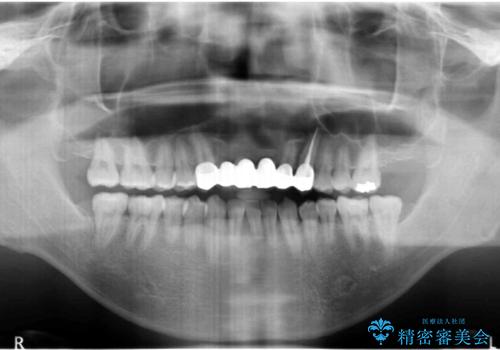

- 前歯のブリッジのやりかえおよび銀の詰め物をセラミックにしたいと来院。

過去に事故で前歯を折って、ブリッジにしたとのことでしたが、支台となる歯が持たない状況で、ブリッジを延長せざるを得ない状況でした。

長いブリッジへ設計変更になるため、下の前歯のがたつきが気になるのであれば、先に矯正治療をしてから最終的なブリッジを入れることをご提案し、全て行なっていくことになりました。

上の前歯の本数が少ないことから、小臼歯を4本抜歯するのではなく下の前歯を1本だけ減らして並べました。

総合歯科治療をやりきったことで、メンテナンスに移行することができました。

左上1番は再根管治療を行いましたが途中で破折が確認されたため、抜歯しています。

また、大臼歯の銀歯もセラミックに全てやりかえています。

左上7番は歯周病によりやむなく抜歯となり、インプラントをおすすめしましたが、希望されませんでした。